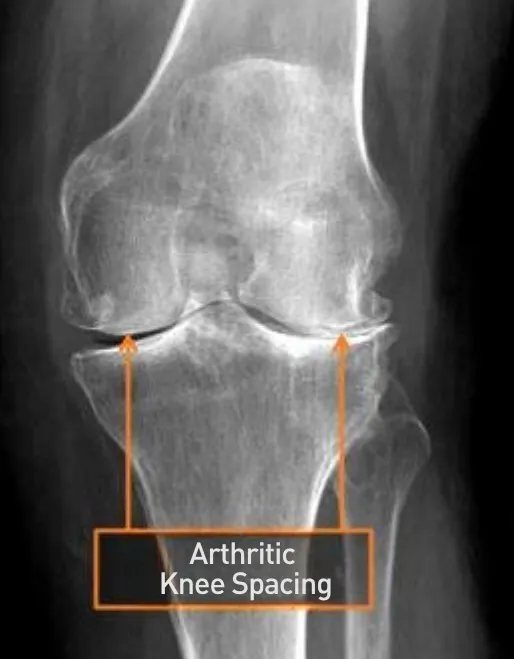

Ignoring knee pain often leads to worsening joint damage, reduced function, and increased discomfort. Conditions like arthritis, meniscus tears, tendonitis, bursitis, or persistent crunching and popping sounds are common contributors to knee pain, making even basic movements a challenge.